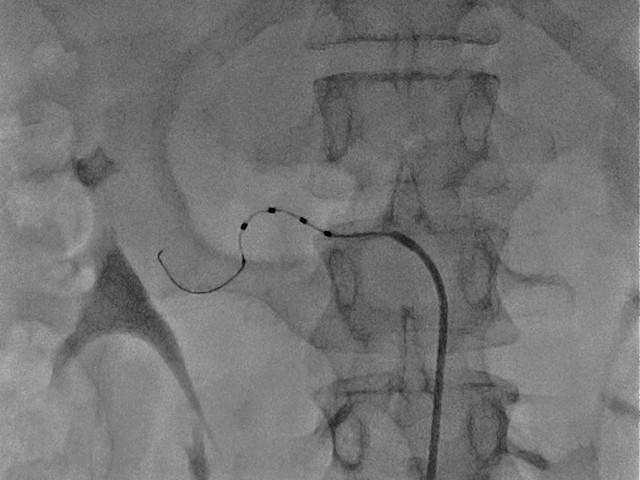

Per la prima volta nel Sannio nel laboratorio di Emodinamica è stato eseguito un intervento di denervazione percutanea delle arteria renali dai dottori Bruno Petruzziello ed Eugenio Laurenzano.

“E’ una tecnica mini-invasiva - ha spiegato il primario Bruno Villari - che, con l’ausilio di un catetere a radiofrequenza, interrompe le terminazioni nervose che decorrono sulle arterie renali, iperattive nei pazienti ipertesi. Con un ricovero di pochi giorni, la denervazione renale si pone l’obiettivo di garantire al paziente trattato, entro un mese, un migliore controllo della pressione arteriosa, permettendogli di ridurre il numero di farmaci assunti e/o il dosaggio degli stessi ed in alcuni casi anche determinandone la sospensione. Questo significa ridurre innanzitutto gli effetti collaterali legati all’assunzione concomitante di più farmaci, ma soprattutto di abbassare notevolmente il rischio cardiovascolare del paziente”.